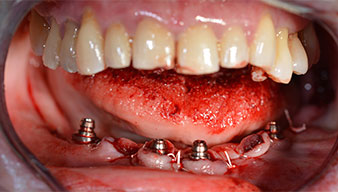

Para compensar la divergencia de los implantes distales, se atornillaron pilares acodados (35 grados) de forma que los perfiles de emergencia de todos los implantes quedaran en la posición más vertical posible en relación con la mordida. Este paso es necesario para poder atornillar de forma oclusal el tratamiento provisional y, posteriormente, el definitivo (figs. 15 y 16).

Implantes

Fig. 15

Fig. 16